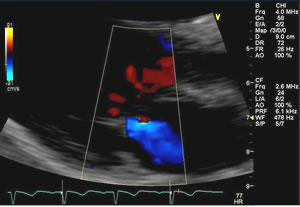

An echocardiogram, known also as a cardiac ECHO or ECHO, is a widely used, non-invasive cardiac diagnostic test. This quick, highly accurate test is relatively inexpensive and uses ultrasound to create two- and three-dimensional images of a patient's heart, allowing doctors to assess the size and shape of the heart, the heart's pumping capacity, any tissue damage or abnormalities, and much more. By performing and properly reading an ECHO, doctors can determine whether chest pain or other symptoms are related to heart disease and can then decide on the best course of treatment.